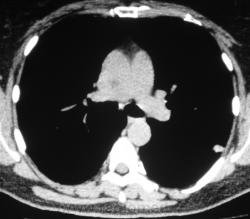

Произведена КТ.

КТ хотелось бы посмотреть в dicom-формате, меняя режимы, но на мой взгляд образование содержит известковые включения. Хотя, я не настаиваю, дождемся мнения коллег.

Нет "волшебных методов", можна поставить диф. ряд. Я бы дала такое заключение: хондрогамартрома, дифференцировать с туберкуломой, периферический рак менее вероятен. Можно жизнь прожить с гамартромой, а может озлиться в саркому. На практике был случай, когда лет 10 наблюдалась классическая скиалогически туберкулома, которая за полгода выросла и оказалась аденокарциномой. Таким образом, при любом раскладе, хирургическое лечение не является ошибкой, но решение об операции на легком должен принимать консилиум.

Дело не в желании, а в смысле. Что тут ещё можно сказать? На мой взгляд-мелкая, частично кальцинированная туберкулома.

Да, более туберкулёма.